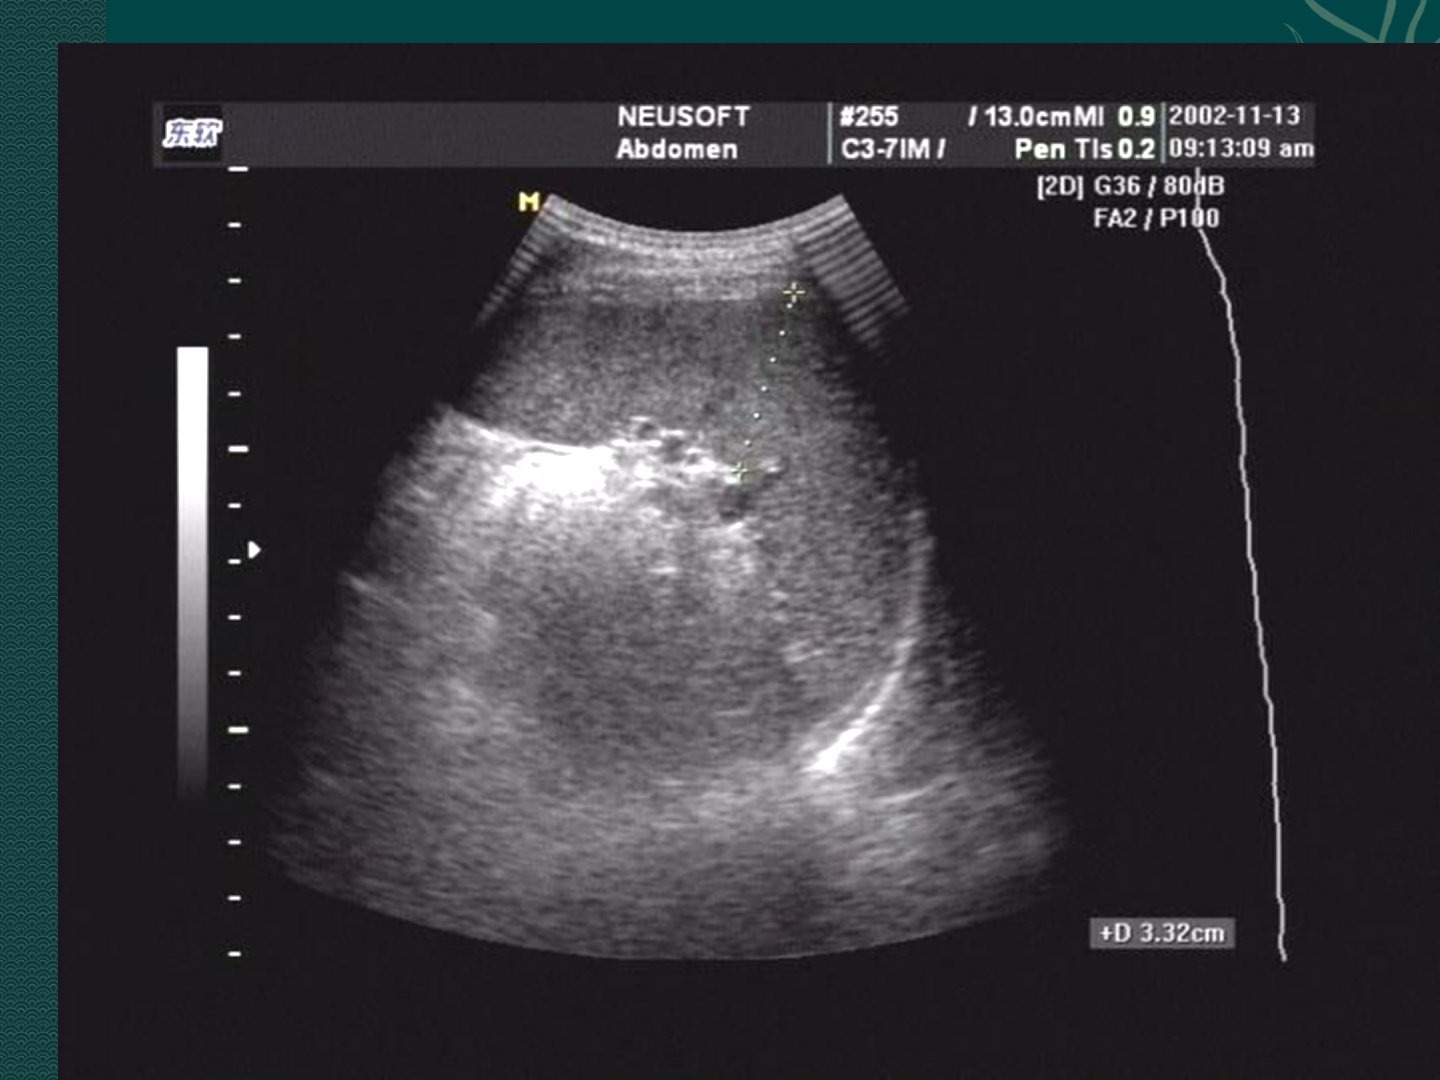

脾脏超声诊断要点如下:正常脾脏肋间呈半月形冠状切面呈三角形包膜光滑脏面有切迹脾实质呈均匀细密中等回声厚径约4cm长径约6cm。脾脏肿大多为继发性二维超声显像即可诊断。脾脏囊肿分真、假性超声可见脾实质内圆形、椭圆形无回声区后方回声增强。脾脏原发性肿瘤少见分良、恶性良性以血管瘤多见表现为边界清晰的偏高回声团有“网络状”表现;恶性以淋巴瘤多见表现为单个或多个低回声结节。脾梗塞超声表现为脾内低回声区形态不规则回声不均。脾脓肿少见常继发于感染超声初期表现为病灶边界不清内部回声不均质中期液化坏死后表现为无回声区。脾外伤分包膜下血肿和脾破裂前者包膜下扁长形无回声区易漏诊;后者包膜不完整形态失常易漏诊小裂缝状破裂。